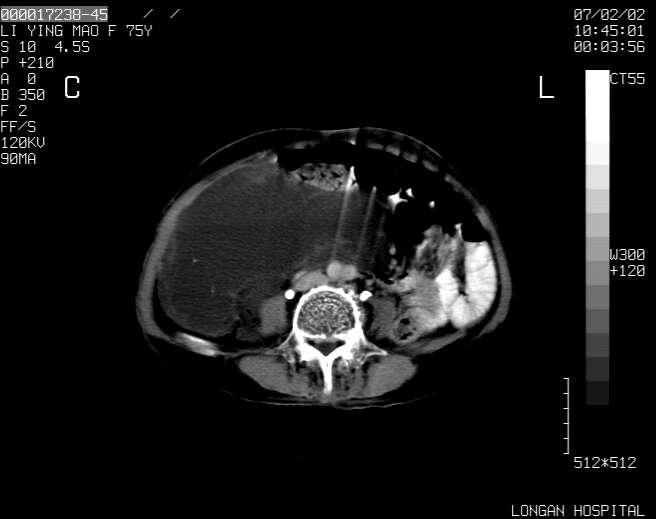

以下是引用dyqct在2007-2-10 8:53:00的发言:[br]考虑:1、肝脏多发囊肿[br] 2、左肾囊肿,右肾多发结石并积水。[br] 3、右胸少量积液。[br] 4、右肾周包裹性积液或淋巴管瘤(有见缝就钻的征象、薄隔、小结节状钙化)?[br] 5、腰椎动脉瘤样骨囊肿?[br] [br] [br]